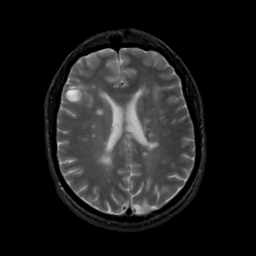

MR Study #8, March 31, 1991 -- Slice #31